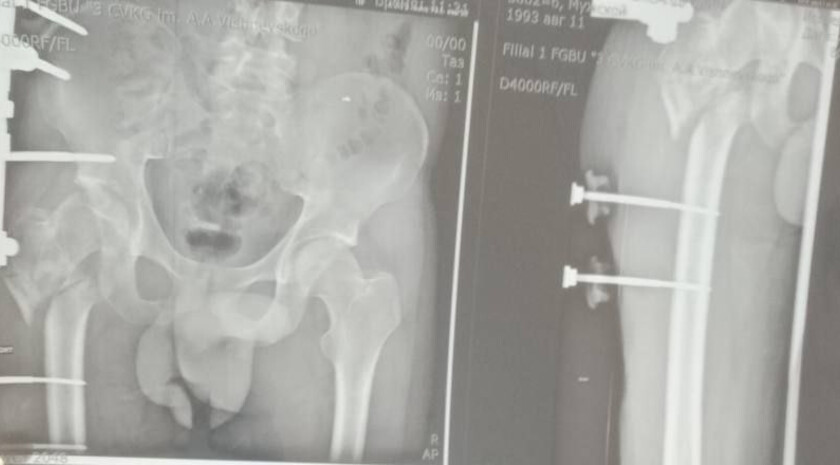

Руководитель Минздрава рассказала, что борьба с травмой сержанта из ЛНР длилась три с половиной года. За это время он проходил лечение в десяти госпиталях, в том числе в Москве и Санкт-Петербурге. В июле 2024 года военнослужащий, удостоенный медали «За отвагу», был уволен со службы по состоянию здоровья. Из-за обширных повреждений и многократных операций правая нога бойца стала короче левой на восемь-девять сантиметров. Обычное эндопротезирование изменить ситуацию не могло.

«Вместо стандартной замены сустава пациенту выполнили сложнейшее вмешательство с использованием ревизионных систем эндопротезирования, в ЛНР такую операцию провели впервые», — цитирует Пащенко ЛИЦ.

Она уточнила, что главная задача хирургов заключалась не просто в установке импланта, а в восстановлении биологической оси конечности и компенсации укорочения.